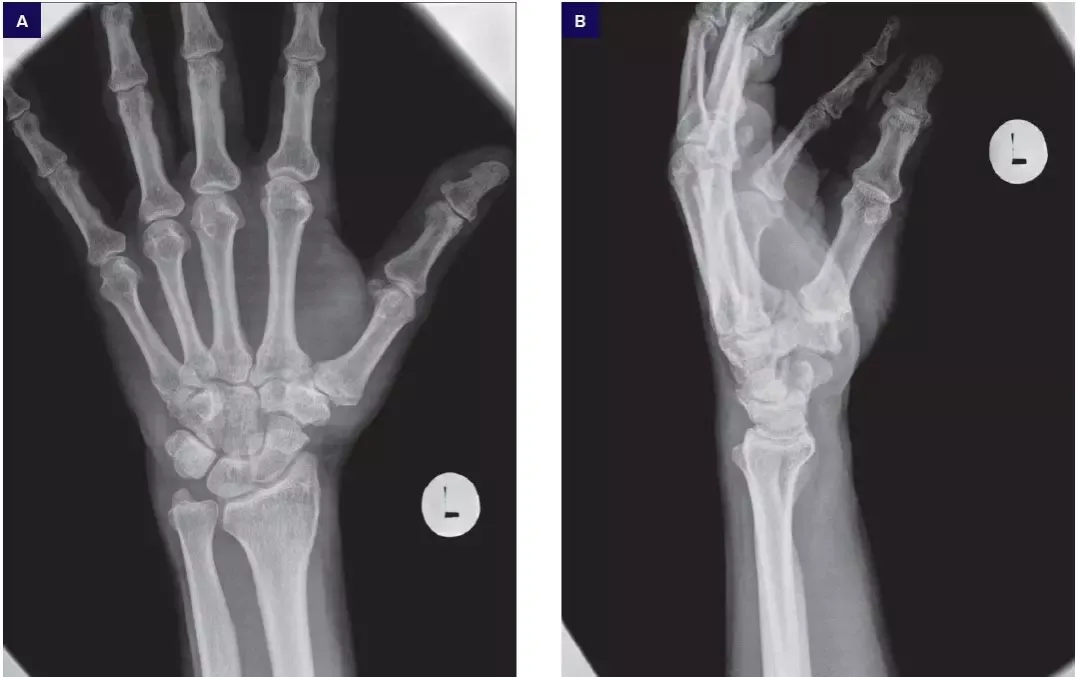

- Podstawowe badania obrazowe. Najczęściej zlecane jest RTG rąk. To badanie jest niezwykle ważne, ponieważ pozwala uwidocznić charakterystyczne zmiany zwyrodnieniowe, takie jak zwężenie szpar stawowych (świadczące o utracie chrząstki), osteofity (wyrośla kostne) oraz geody (torbiele podchrzęstne).